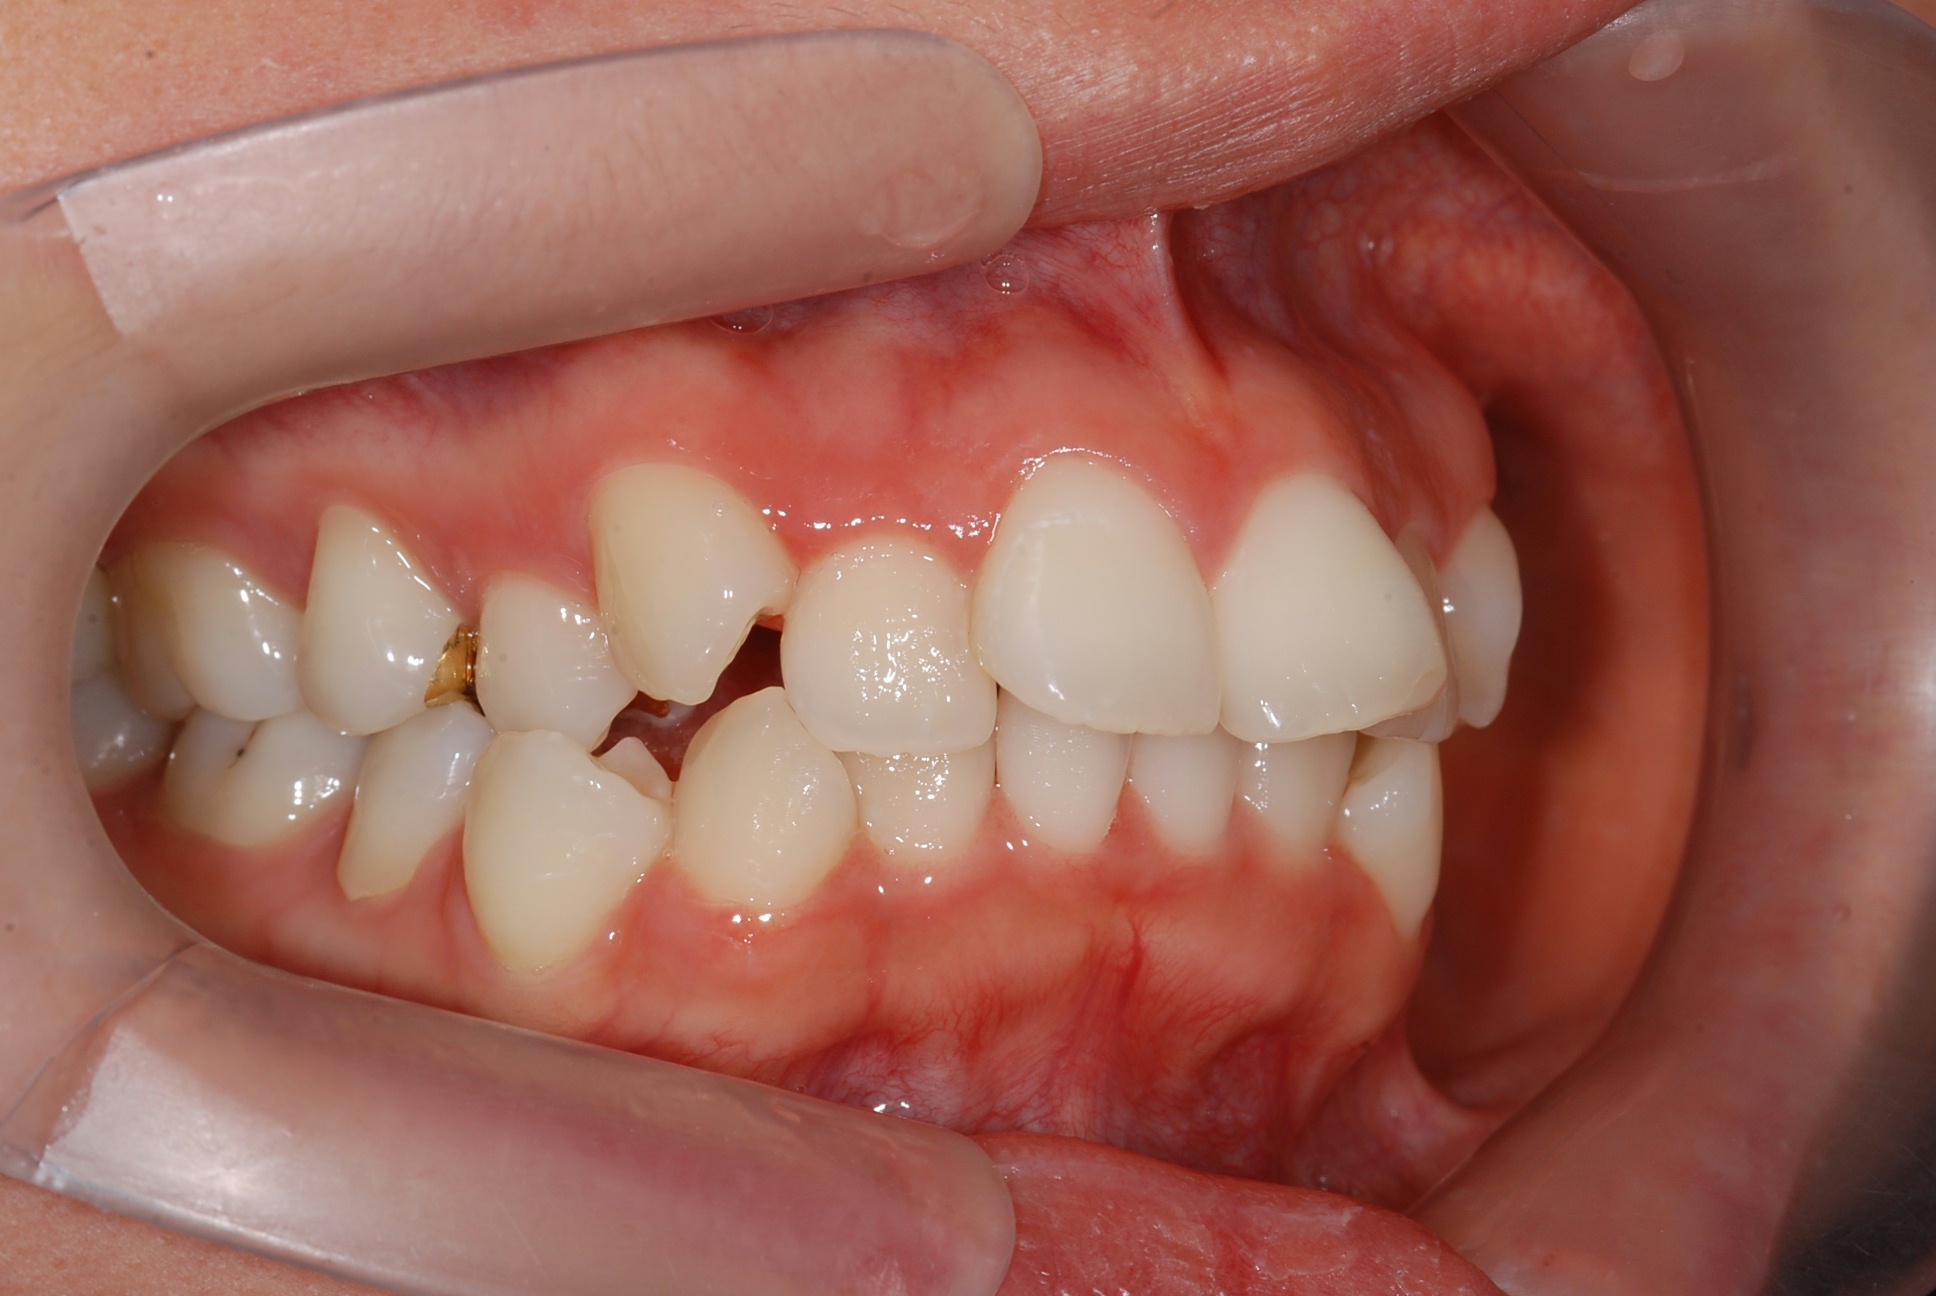

치료 후 사진입니다.